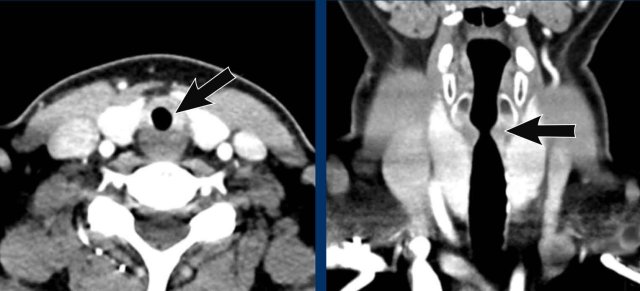

Image

Incidental tracheal

bronchus in a 28 y.o male scanned for oncology follow-up (axial image) and in a 77 y.o male scanned in trauma setting (coronal image).